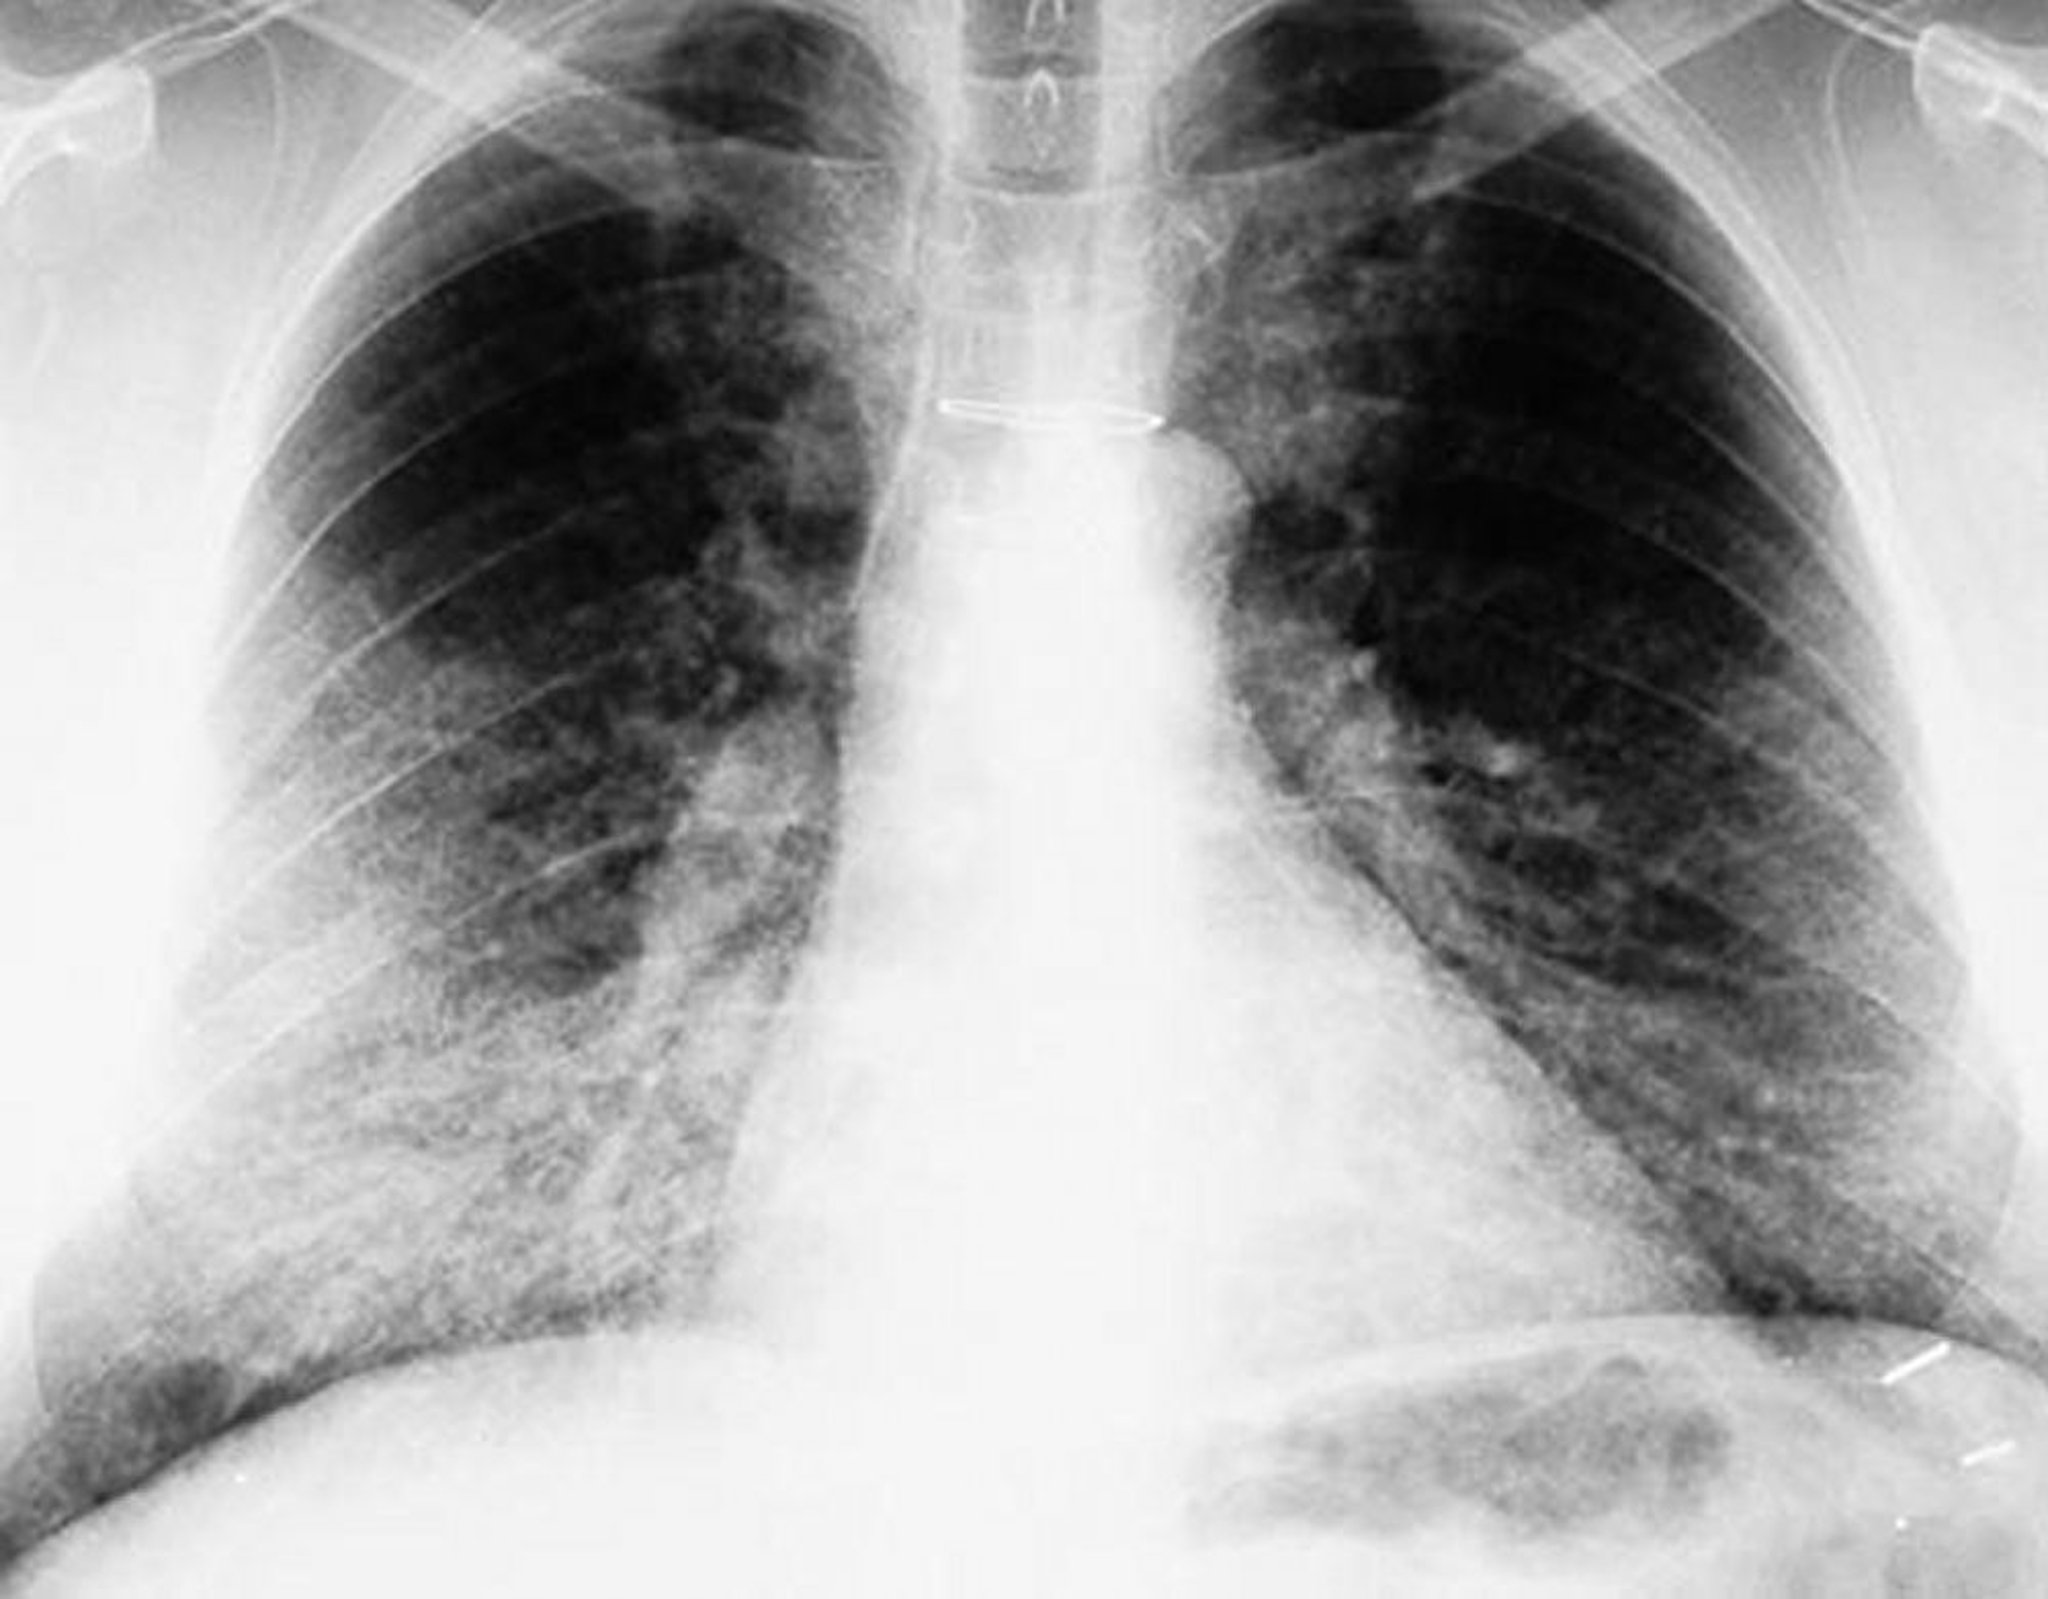

Proteinosi alveolare polmonare (RX torace)

La RX torace mostra opacità bilaterali, prevalentemente basilari.

By permission of the publisher. Da Lynch III J, Myers J. In Bone's Atlas of Pulmonary and Critical Care Medicine. Edited by J Crapo. Philadelphia, Current Medicine, 2005.